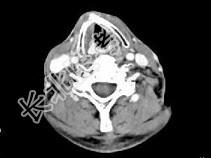

- 单项选择题男,63岁, 咽喉部不适约1年,近两个月经常咳嗽, 痰中带有血丝,CT如图所示, 最可能的诊断是 ( )

A、梨状窝癌

B、声门型喉癌

C、声门下型喉癌

D、声门上型喉癌

E、混合型喉癌